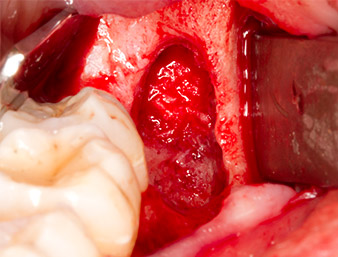

Il tessuto al di sopra del residuo di radice non era completamente ossificato ed era costituito per la maggior parte da tessuto di granulazione modificato dall'infiammazione (Fig. 4).

È stato inoltre rimosso tessuto periapicale infiammato, molto attentamente con un escavatore manuale. La Figura 12 mostra l'alveolo vuoto con il nervo alveolare inferiore esposto.